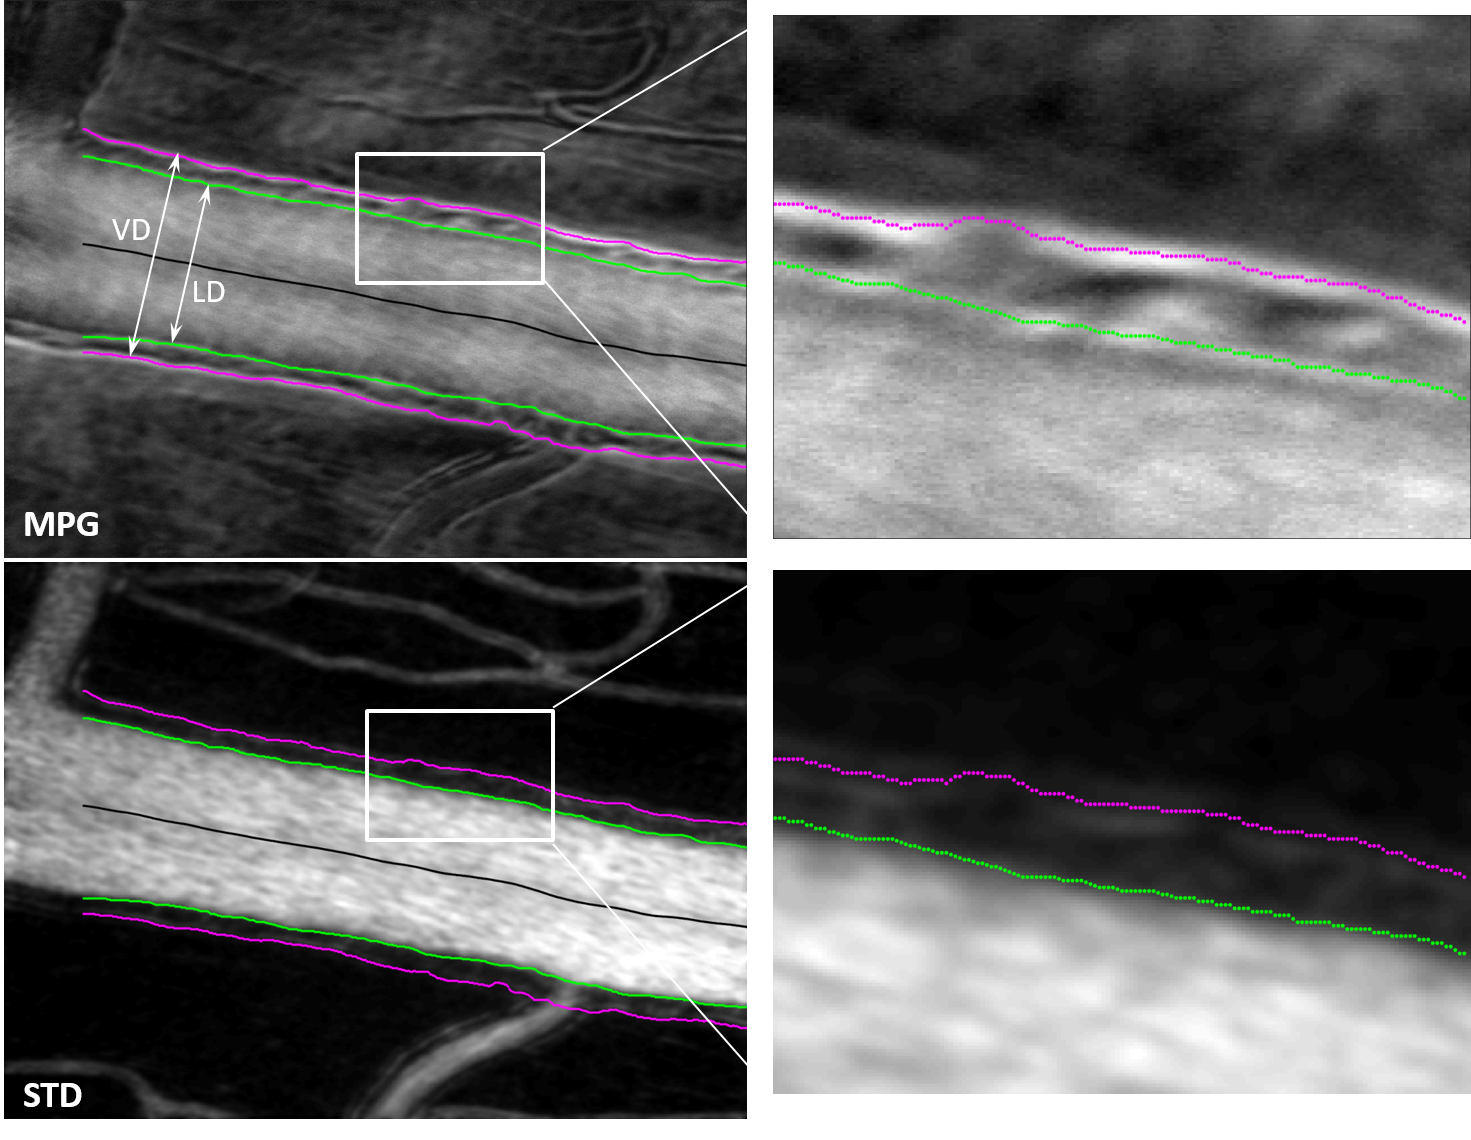

Phase gradient segmentation

“Cellular-Level Analysis of Retinal Blood Vessel Walls Based on Phase Gradient Images”, Diagnostics, 13(22), 3399, (2023)